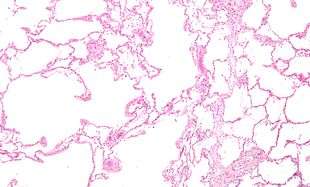

COPD is a type of obstructive lung disease in which chronic incompletely reversible poor airflow (airflow limitation) and inability to breathe out fully (air trapping) exist.[5] The poor airflow is the result of breakdown of lung tissue (known as emphysema) and small airways disease (known as obstructive bronchiolitis). The relative contributions of these two factors vary between people.[1] Severe destruction of small airways can lead to the formation of large air pockets—known as bullae—that replace lung tissue. This form of disease is called bullous emphysema.[52]